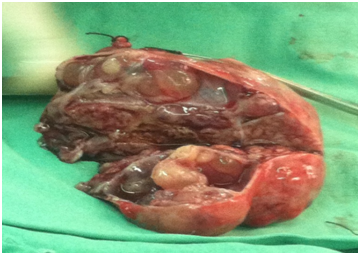

A two years old girl presented with history of urinary retention since 2 months. It was associated with decrease urinary output and painful micturation since 1 month. She also had a history of gradual abdominal distention with mild abdominal pain. She is a product of consanguineous marriage with death 2 of her preceding sibling due to unknown reasons at age of 3 months and 2 years. Her general physical examination was normal. Her abdominal examination showed massive abdominal distention with positive fluid thrill and shifting dullness. A rounded, fixed mass felt at the pelvic area with smooth surface. Her rectal examination showed tenderness at the anterior rectal wall. She had normal breast and genetalia. Normal blood & urine tests. Abdominal ultrasound showed a mixed echogenicity mass measuring 11.5x6.7cm with both solid and cystic components arising from the pelvic area with gross ascites. Contrast enhanced CT scan shows massive ascites and a large, heterogenous, solid cystic mass in lower abdomen & false pelvis (11x8.1x7.5cm); originating from the left adenxa with no internal calcification. There was associated with abdomen-pelvic ascites. Rest of abdominal viscera, peritoneium and lymph nodes were unremarkable. Her Alfha fetoprotein and bHCG were normal. On exploratory Laprotomy 1 liter of Ascitic fluid was drained with samples sent for analysis. Left salpingo-opherctomy was done as the mass was originating from the left ovary Figure 1. Uterus, right ovary and lymph nodes were grossly normal. Peritoneal fluid cytology was negative for malignant cells. Grossly the mass was having mixed cystic and solid areas, weighting 1.3kg with some focal areas of hemorrhage Figure 2. Histopathological examination Microscopic features show diffuse sheets and macrofollicular pattern of tumor cells. The malignant cells were polygonal and small. The cytoplasm was abundant and amphophilic. The nuclei were atypical without grooves and show conspicuous nucleoli at places. Mitotic activity was more than 10 cells/10 hpf. Large tumor cells with extensive lutenization were seen focally, presenting the cal component of ovarian stroma that is compatible with Juvenile granulosa cell tumor Figure 3. Immuno-histo-chemistry was positive for Inhibin and CD99 and negative for EMA, CD117 and alpha feto-protein. Bone scan and chest radiographs were unremarkable. Based on FIGO staging system this patient is stage IA. On 3 months follow up patient is doing well and her urinary retention relieved, however she is on long term follow up due to late recurrence.

Figure 1 Intra-operative picture showing the mass originating from the left ovary with intact capsule.

Figure 2 Gross picture of the tumor showing solid and cystic structures.